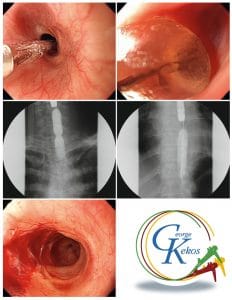

Διαστολές με μπαλόνια: Η τελευταία κατάκτηση είναι η διαστολή που υλοποιείται υπό άμεσο ενδοσκοπικό έλεγχο με τους υδροστατικούς διαστολείς, οι οποίοι εισάγονται μέσα από το κανάλι εργασίας του ενδοσκοπίου (Through the scope balloon catheters: TTS balloon). Αυτοί αποτελούν τροποποίηση του καθετήρα με μπαλόνι, που περιγράφηκε το 1974 από τους Gruntzig και Hopff, για τη διαστολή των αγγείων.

Η ενδοσκοπική διαστολή των στενώσεων με καθετήρες-μπαλόνια είναι μια ασφαλής, αποτελεσματική και καλά ανεκτή θεραπευτική μέθοδος, που απαιτεί λίγα μόνο λεπτά για κάθε συνεδρία. Γίνεται υπό άμεση ενδοσκοπική όραση και δεν απαιτείται η χρήση ακτινολογικού μηχανήματος. Οι δυνάμεις που ασκούνται από το διατεταμένο μπαλόνι είναι στατικές με ακτινωτή διάταξη και απόλυτα ελεγχόμενες. Το γεγονός αυτό καθιστά τις διαστολές με μπαλόνι πιο αποτελεσματικές και ιδιαίτερα κατάλληλες για τις στενώσεις με μεγάλο μήκος.

Ο ασθενής τοποθετείται σε θέση γαστροσκόπησης. Για την ευχερέστερη διέλευση των διαστολέων, χρησιμοποιούνται ευρυκάναλα θεραπευτικά ενδοσκόπια (3,8 mm). Με την ενδοσκόπηση εντοπίζεται η στενεμένη περιοχή και, με βάση την υπολογισθείσα διάμετρο, επιλέγεται και το μέγεθος του μπαλονιού με το οποίο αρχίζει η διαστολή. Αφού ο καθετήρας-μπαλόνι επαλειφθεί με γέλη λιπαντικής ουσίας, προωθείται μέσα από το κανάλι εργασίας του ενδοσκοπίου και στη συνέχεια στη στένωση, έτσι ώστε το μπαλόνι να βρίσκεται σε όλο το μήκος της στένωσης.

Με το μπαλόνι τοποθετημένο στη στένωση, διοχετεύεται νερό για να διαταθεί, ενώ ταυτόχρονα ελέγχεται με το μανόμετρο η προβαλλόμενη δύναμη. Μόλις επιτευχθεί το ανώτατο επιθυμητό όριο πίεσης, κλείνεται η στρόφιγγα επικοινωνίας του μπαλονιού με το υπόλοιπο σύστημα.